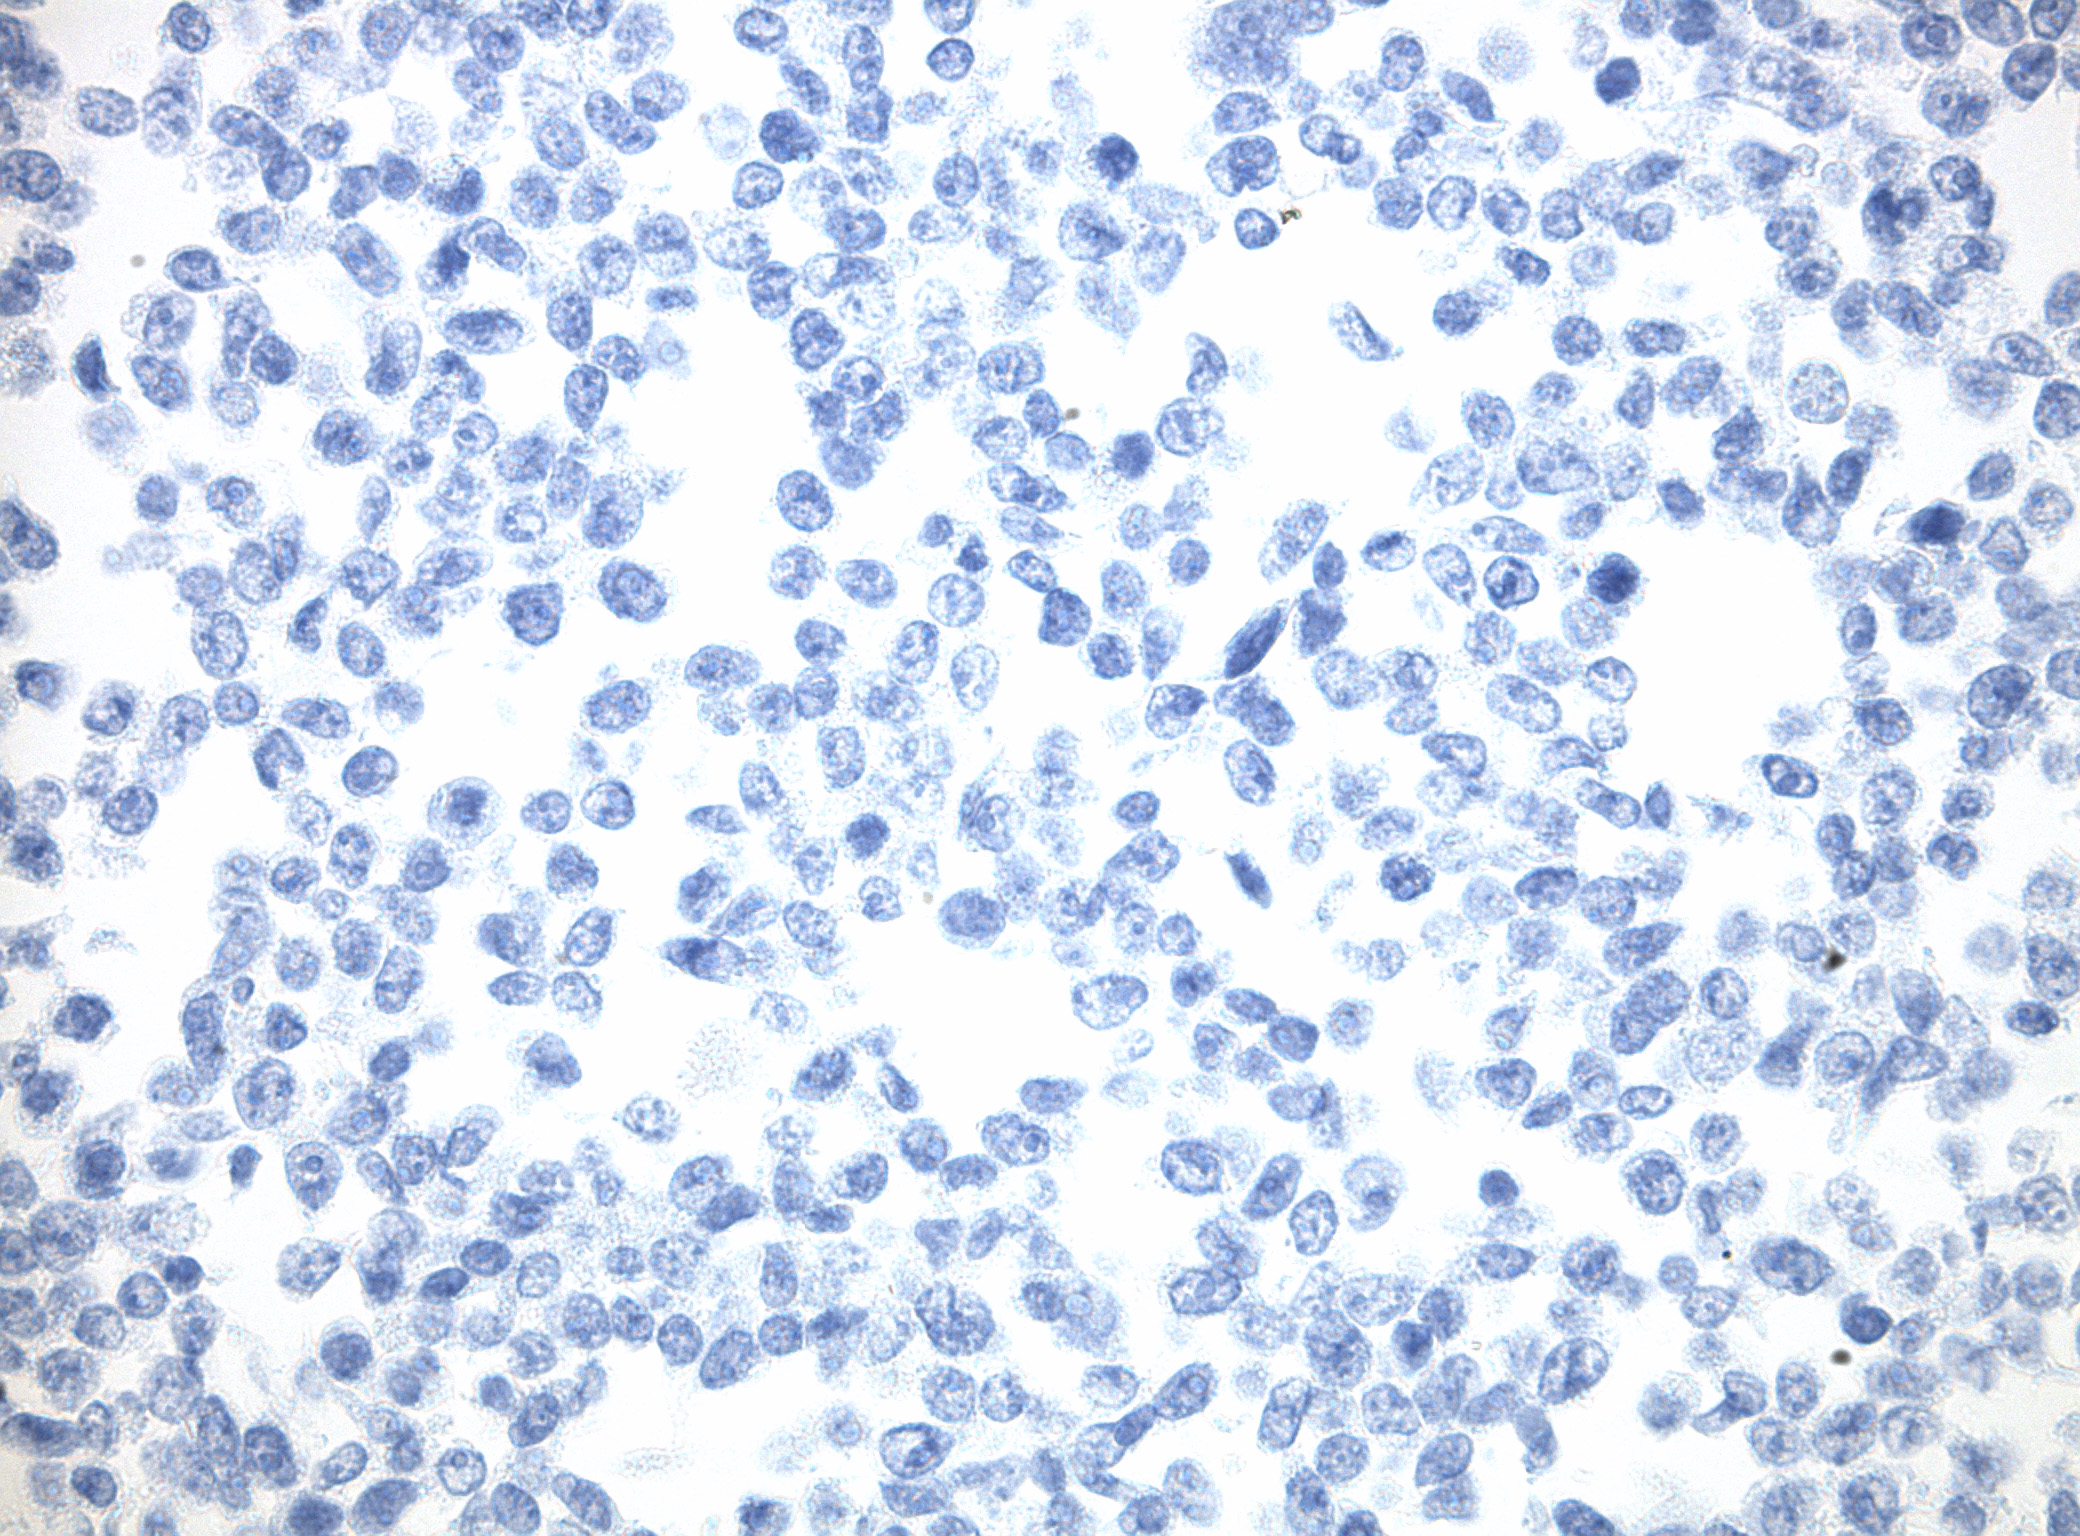

IDH1 (R132H) Mutant-Specific Antibody Screening, Validation, and Specificity

CytoSections enables identifying the right antibody for your research. See how CytoSections, featuring WT or mutant IDH1 (R132H) protein, helped screening and validation of specific antibody against the mutant IDH1 (R132H).

CytoSections |

IDH1 (WT) |

IDH1 (R132H) |

IDH1 (WT) |

IDH1 (R132H) |

|

IDH1 (R132H) Antibody |

Reactivity |

None |

Strong |

None |

Mild |